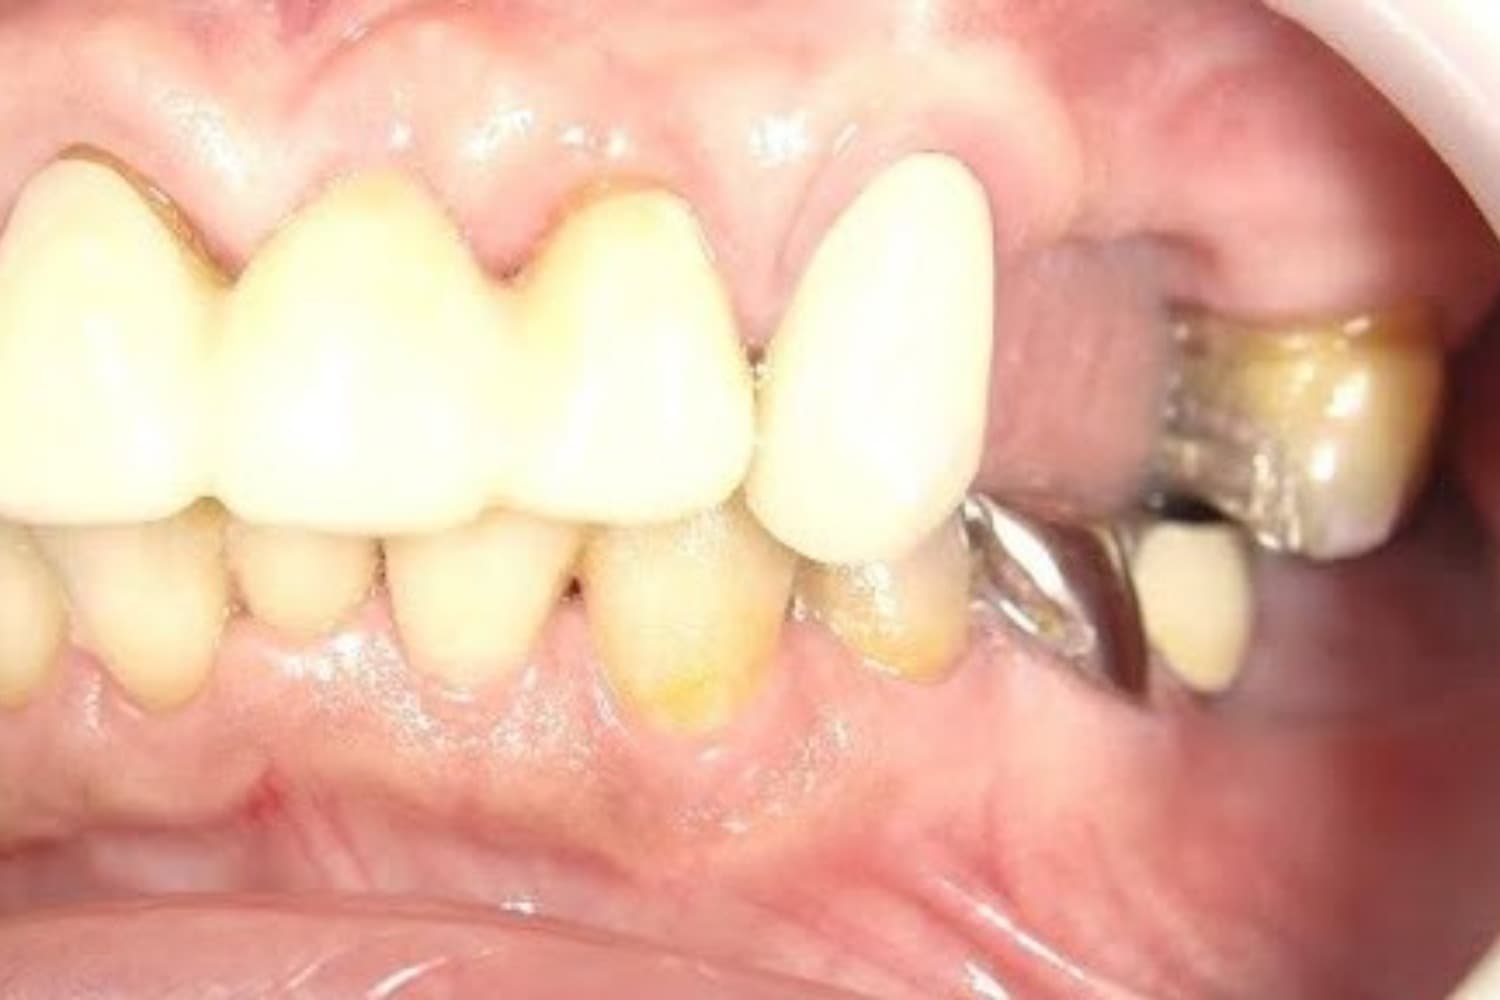

左上の歯のインプラント治療(60代女性)

Before

インプラント抜歯即時埋入・即時荷重(抜歯と同時にインプラントを埋入し、当日に仮歯を入れる)

60代

女性

重度の歯の動揺があり、何もしていなくとも痛みがある。治療にあたって前歯がないことを気にする。

4ヵ月

10回

814,000円(税込) 費用の内訳: 【インプラント基本料】330000円×2=660000円(税込み) 基本料金に以下を含む ・フィックスチャー及び手術費用 ・投薬費用、 ・レントゲン費用 ・インプラント上部費用(アバットメントおよびジルコニアクラウンの費用用) 【オプション費用】 ・右上5グラフトレスサイナスリフト費用 33000円(税込み) ・右上3抜歯即時荷重費用 33000円(税込み) ・暫間インプラント費用 0円